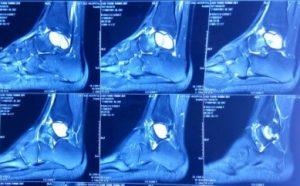

Hình ảnh nang xương phình mạch xương sên trên phim cắt lớp vi tính, cộng hưởng từ. Ảnh: BVCC. |

Chụp X-quang, bác sĩ nhận thấy ổ khuyết xương lớn chiếm gần toàn bộ thân xương sên trái. Bệnh nhân được chỉ định chụp cắt lớp vi tính nhằm đánh giá mức độ phá hủy vỏ xương, kết quả nang xương lớn chiếm toàn bộ thân xương sên, chưa phá hủy vỏ xương. Đồng thời, bệnh nhân được chụp cộng hưởng từ đánh giá tính chất u.